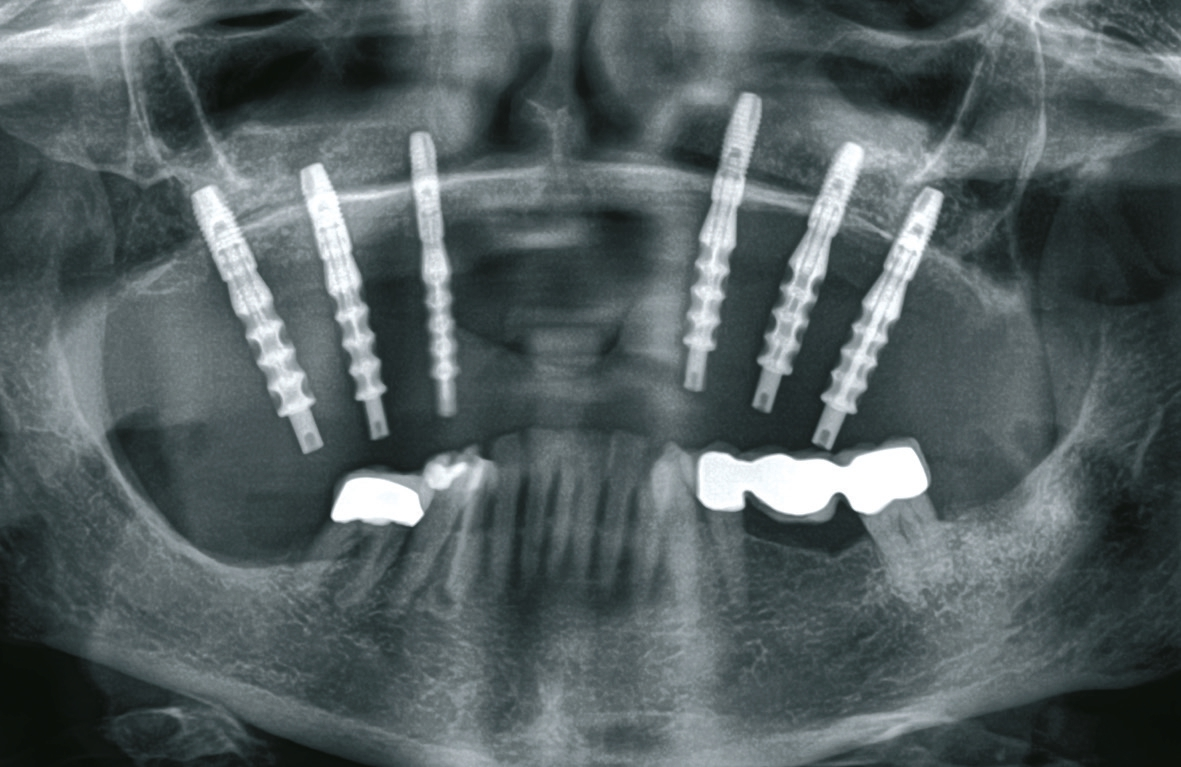

Vor dem zweiten OP-Eingriff nach 4 Monaten wurde im Labor eine Bohrschablone hergestellt. Zudem wurde ein DVT angefertigt, um im Sinne eines backward planning die idealen Implantatpositionen zu ermitteln. Bei Eröffnung des augmentierten Kieferbereiches zeigte sich eine gute Regeneration und Revaskularisierung des Knochens. Sechs Implantate konnten mit ausreichender Länge und passendem Durchmesser so in den augmentierten Bereich (Astratech EV®, Dentsply Sirona Implants, Mannheim) inseriert werden, dass sich eine gleichmäßige Pfeilerverteilung ergab (Abb. 7 u. 8).

Bei der Eingliederung des Steges wurde festgestellt, dass das Implantat regio 27 nicht osseointegriert war. Möglicherweise war dies auf eine ungenügende Regeneration des in dieser Region verwendeten Knochenersatzmaterials im Rahmen des Sinuslifts zurückzuführen. Das nicht osseointegrierte Implantat wurde folglich entfernt, ebenso das nicht umgewandelte Knochenersatzmaterial (Abb. 17). Daraufhin wurden mit der Luerzange autologe Knochenpartikel aus dem Tuber entnommen und in Region 27 appliziert. Der Zahntechniker kürzte die Stegarbeit ein (Abb. 18), die nun nur auf den 5 gut osseointegrierten Implantaten ruhte. Während der kompletten Ausheilungsphase im Bereich des entfernten Implantates regio 27 konnte die Patientin die angepasste Stegarbeit weitertragen. Nach 3 Monaten erfolgte der Re-entry in dieser Region. Der Situs zeigte sich gut verheilt (Abb. 19a u. b), der Knochen war gut regeneriert und die Nachimplantation regio 27 wurde vorgenommen (Abb. 20). Nach weiteren 4 Monaten Einheilphase erfolgte die Freilegung des neuen Implantats regio 27. Dieses zeigte sich diesmal gut regeneriert und konnte nun wie geplant der Stegarbeit als sechster Pfeiler dienen.

Die besondere zahntechnische Herausforderung bestand nun darin, das Implantat über ein Abutment in die vorhandene Stegversorgung einzubeziehen. Die genaue Position wurde über eine Abformung mit Laboranalogen bestimmt, kontrolliert durch ein OPG (Abb. 21). Wieder wurde in situ mit einem Übertragungsschlüssel aus Pattern gearbeitet, um das neu zu fertigende Stegstück spannungsfrei anschließen zu können. Nach ausgiebigen Prüfungen wurde die Ergänzung gegossen und nach der Patientenanprobe an den bestehenden Stegbogen angelasert (Abb. 22a u. b, Abb. 23). Es folgte die Herstellung der endgültigen Sekundär- und Tertiärstruktur (Abb. 24). Bei dem hier vorgestellten Patientenfall wurde das Sekundärgerüst herkömmlich gegossen (Brealloy, Bredent, Senden). Lichthärtender Kunststoff sowie Konfektionszähne komplettierten die Arbeit, wobei die Ästhetikanprobe unverändert übernommen wurde.